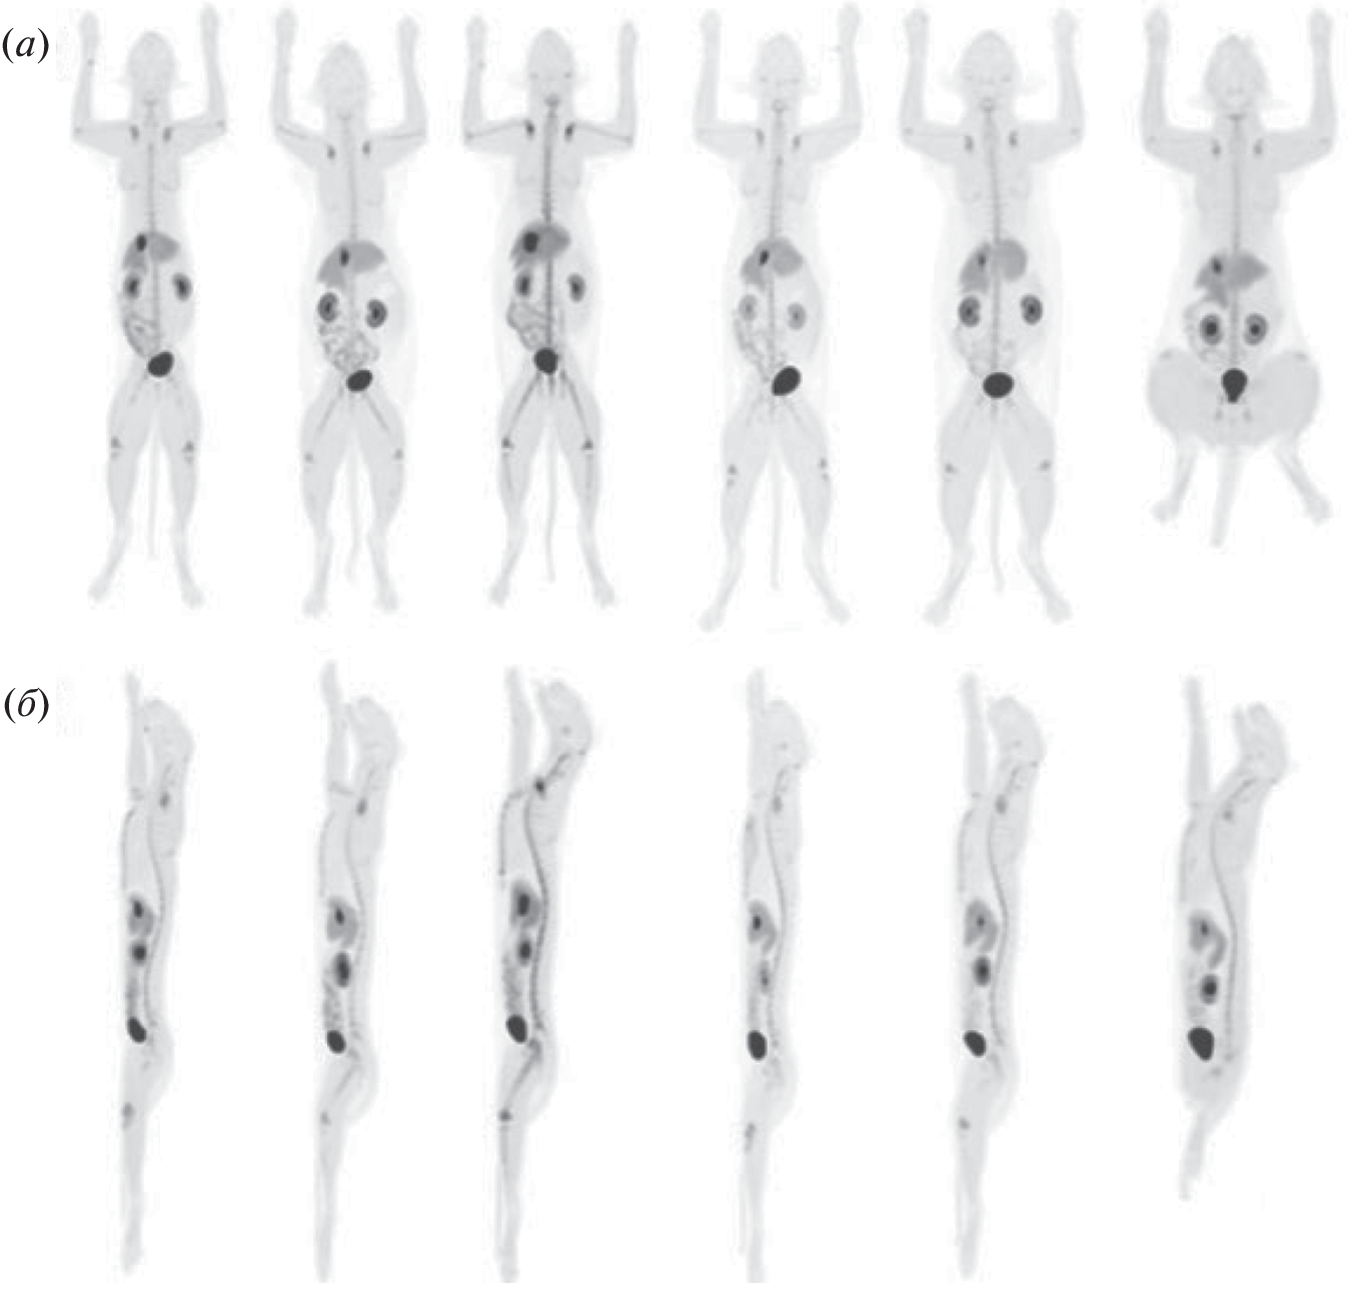

- Rowe J.A., Morandi F., Wall J.S., Akula M., Kennel S.J., Osborne D., Martin E.B., Galyon G.D., Long M.J., Stuckey A.C., LeBlanc A.K. // Veterinary Radiol. Ultrasound. 2013. V. 54. P. 299–306. https://doi.org/10.1111/vru.12024